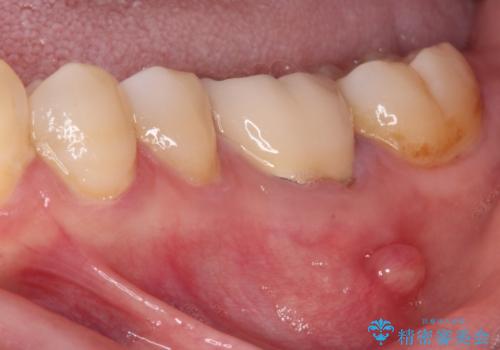

診査したところ、下顎の奥歯は膿の出口ができており、上顎の奥歯は噛んだときに痛みを感じている状態でした。

処置後、下顎の膿の出口はすぐに消えましたが、レントゲン写真からも分かるとおり、歯根途中に穴が開いており、充填材が歯根外にはみ出していました。数ヶ月経過を見たところ、特に異常は認められなかったため、補綴治療を行いました。